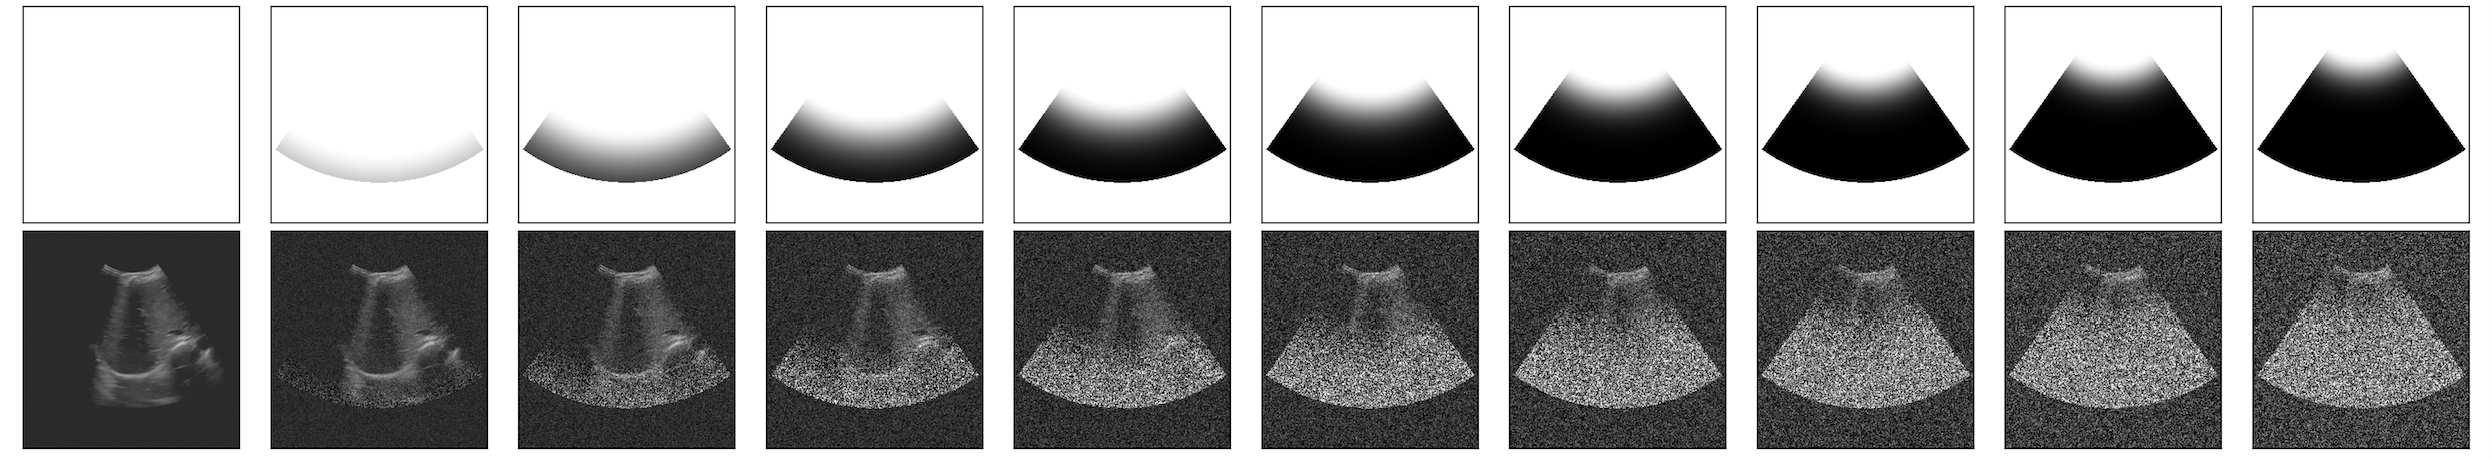

Central to our approach is the introduction of B-Maps; these matrices, have the same dimensions as the US images, and allow for precise control of the noise level at each pixel. The idea is to change how the standard DDPMs introduce noise in the image. While the normal DDPM, originally designed for natural images, applies noise uniformly in the image, the B-Maps scale the noise across the vertical axis of the image, simulating the top-to-bottom image construction of US imaging. Our novel adaptation introduces more noise—and thus, faster convergence towards a standard Gaussian distribution—at the bottom of the image than at the top. As a result, we define a diffusion model that focuses on learning the distribution of the upper region of the image first before addressing the inherently noisier lower region, as the sound waves lose strength the deeper they go into the body. This prioritized learning process ensures that the most reliable details—those closer to the probe—are captured with higher fidelity and we also prevent coming up with artifacts and non-anatomically plausible features. An illustration of the definition of B-Maps is shown in Figure 1.

Refer to caption

Figure 1: Evolution of B-maps across time-steps. In every timestep, the values in the B-Maps decrease top-to-bottom from 1 to a number, γ𝛾\gamma. As the timestep increases, γ𝛾\gamma goes from 1 to 1ϵ1italic-ϵ1-\epsilon, with ϵitalic-ϵ\epsilon being a small fixed value in the interval (0,1)01(0,1).

with: α¯t=t=1Tαt and B¯t=t=1TBtsubscript¯𝛼𝑡superscriptsubscriptproduct𝑡1𝑇subscript𝛼𝑡 and subscript¯𝐵𝑡superscriptsubscriptproduct𝑡1𝑇subscript𝐵𝑡\bar{\alpha}_{t}=\prod_{t=1}^{T}\alpha_{t}\text{ and }\bar{B}_{t}=\prod_{t=1}^{T}B_{t} and \cdot denoting the point-wise multiplication. This method guides the diffusion model’s behavior, introducing noise in the forward process by simulating the progressive attenuation of echo intensity. The visual representation of this modified process is shown in Fig. 2.

Figure 2: Forward pass: Noise addition from bottom to top. Linearly-scheduled cone-shaped B-Maps on the top row and the visualization of the noising process of the US image in the bottom row. B-Maps are applied at each step, making the gaussian distribution converge earlier on the bottom than on the top.